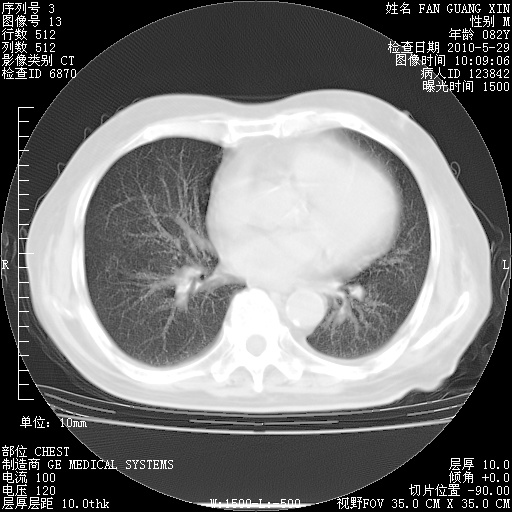

再治疗10天后的肺部CT

从白细胞总数和中性比例看好像合并感染。肺部纹理好像比上次多,支气管炎?其他感染?

阅读此次胸部CT,肺间质渗出性改变较入院时有吸收。目前从体温、白细胞、中性分叶明显增高,肯定存在细菌感染(发生医院感染哦,若无消化道及泌尿系统等感染的依据,肺部感染可能大)。若你院头孢哌酮舒巴坦钠耐药率较高,同意你的方案,若48小时体温仍高,可考虑使用碳青霉稀类抗菌药物,同时可予超声雾化、注意滴数时加大液体量。白蛋白33.30g/L较低哦,需加强营养等支持治疗。